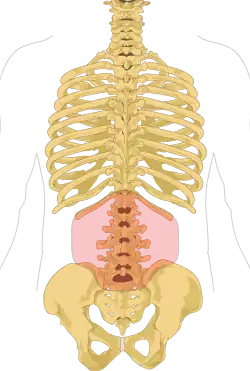

| Location of the lumbar region (pink) in relation to the human skeleton | |

The lumbar (or lower back) region is the area between the lower ribs and gluteal fold which includes five lumbar vertebrae (L1–L5) and the sacrum. In between these vertebrae are fibrocartilaginous discs, which act as cushions, preventing the vertebrae from rubbing together while at the same time protecting the spinal cord. Nerves come from and go to the spinal cord through specific openings between the vertebrae, receiving sensory input and sending messages to muscles. Stability of the spine is provided by the ligaments and muscles of the back and abdomen. Small joints called facet joints limit and direct the motion of the spine.[34]